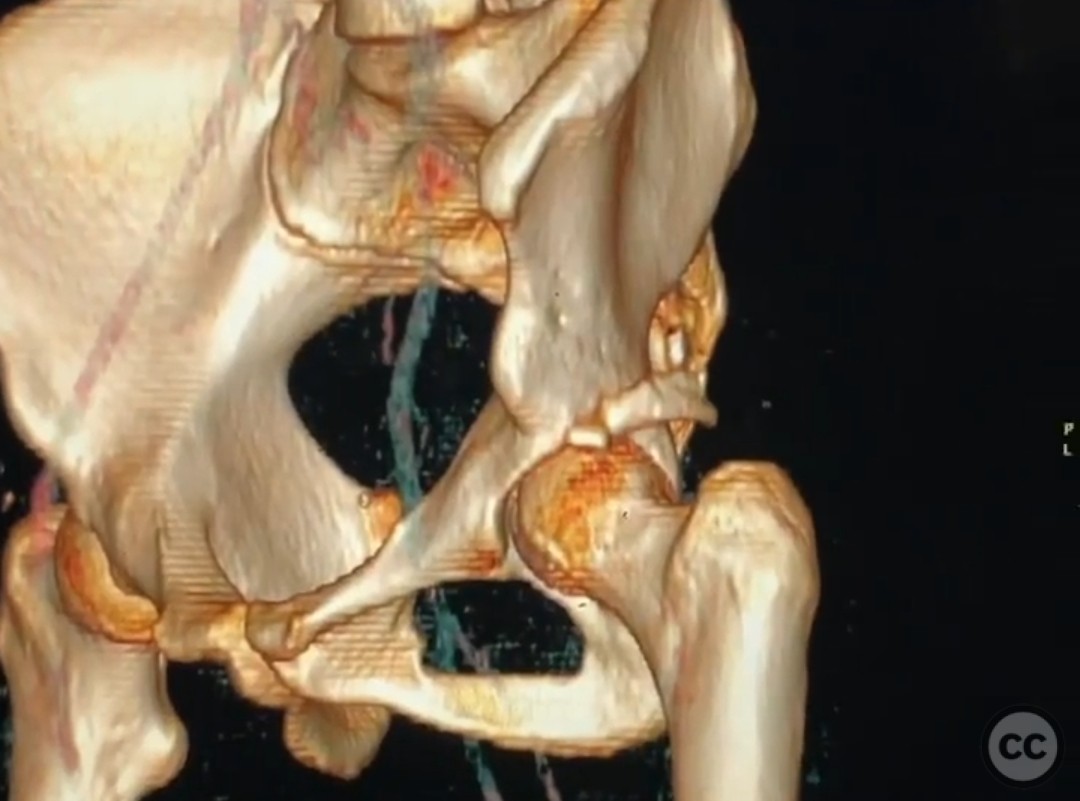

Pipkin IV Femoral Head Fracture with Posterior Wall Involvement and Femoral Neck Fracture.

Clinical and radiological findings:  A 33-year-old female involved in a motor vehicle collision presented with a posterior hip dislocation accompanied by a comminuted supra-foveal femoral head fracture, a cranial peripheral posterior wall fracture, and a non-displaced femoral neck fracture. The injury is associated with a risk of sciatic nerve palsy and avascular necrosis (AVN).